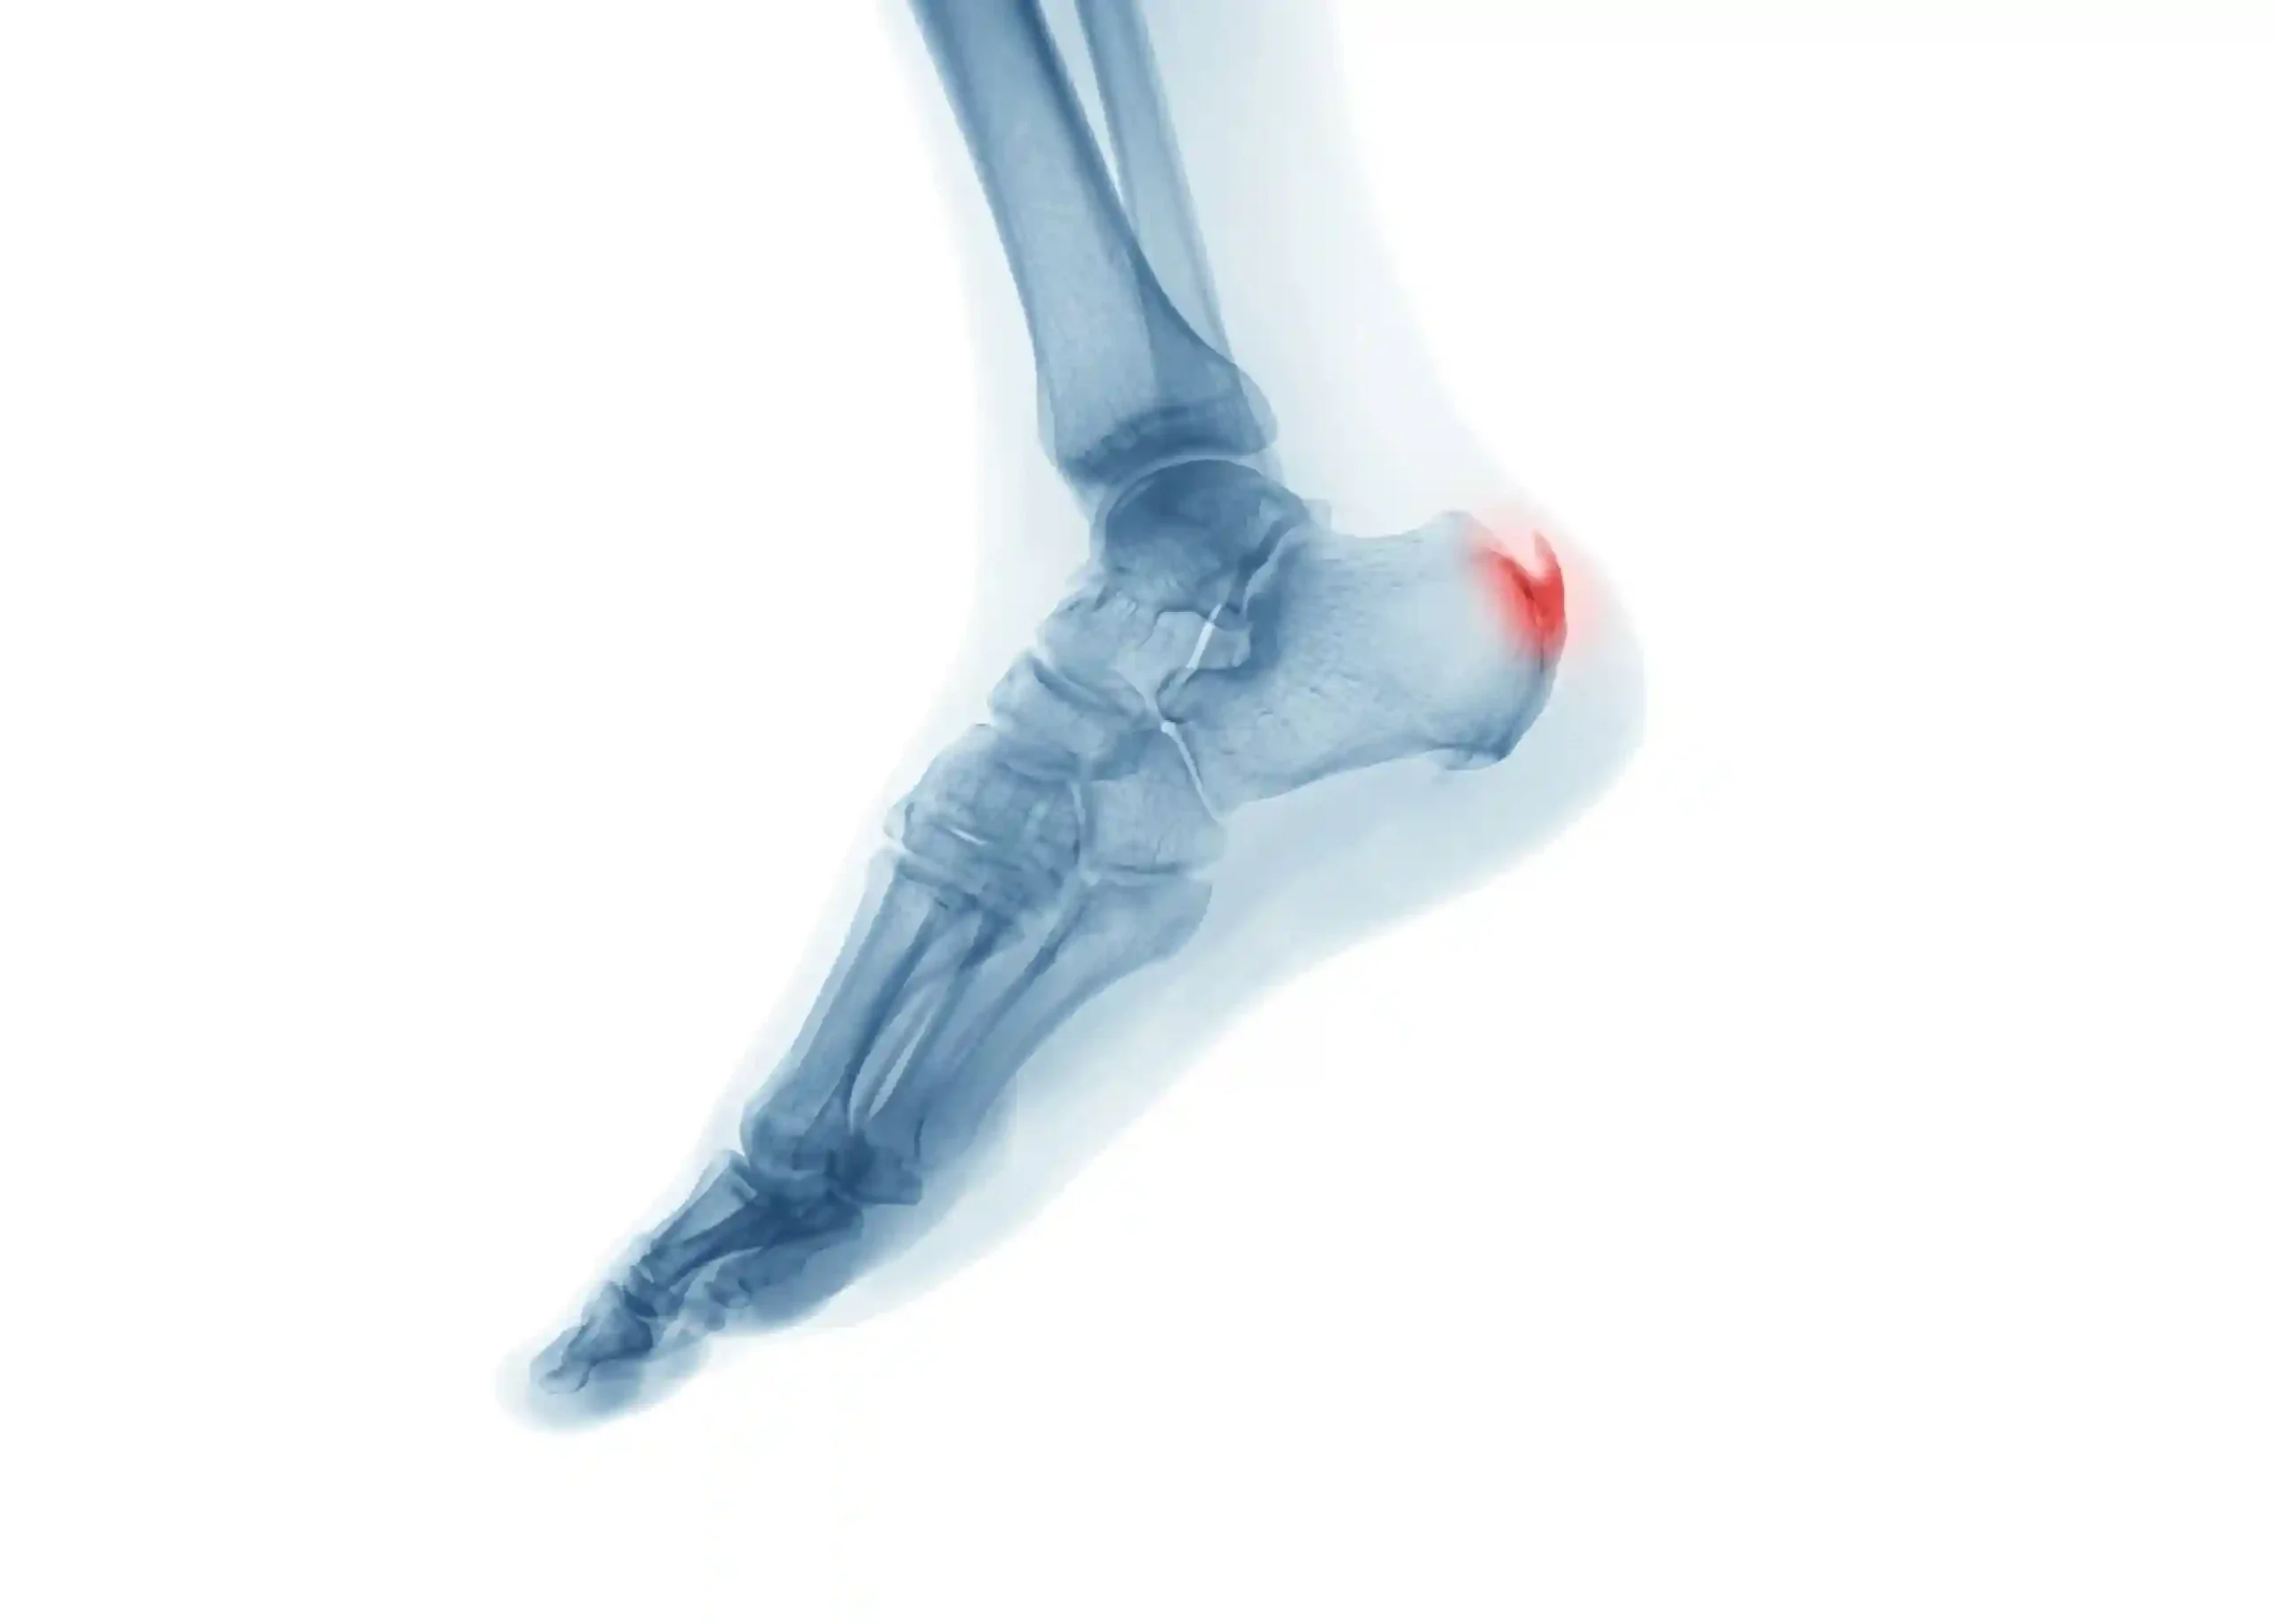

Heel Spur Treatment

Heel spur treatment reduces heel pain and inflammation while improving foot support and helping patients return to comfortable daily movement.

Plantar Fasciitis Treatment

Plantar fasciitis treatment focuses on relieving heel pain caused by inflammation while restoring flexibility, support, and natural foot movement.